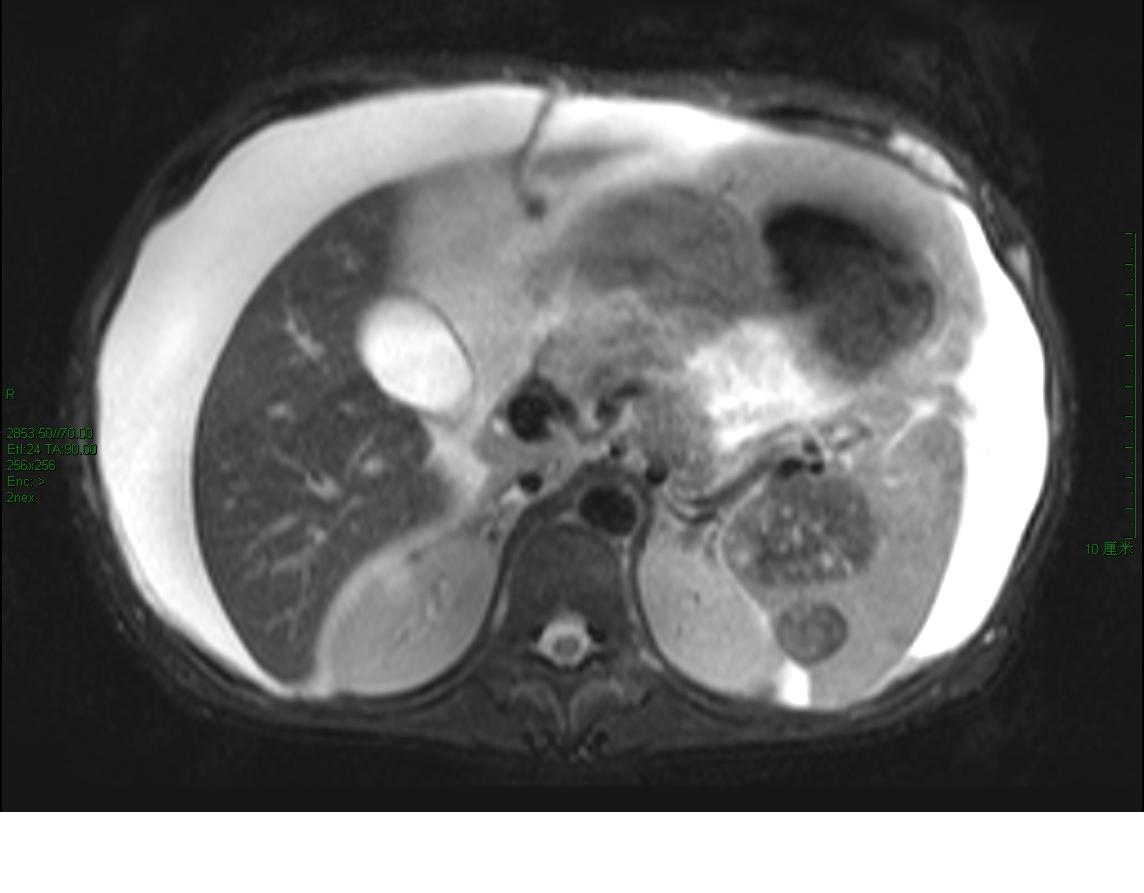

男性,47岁,乙肝病史十余年,无发热、腹痛,无恶性、呕吐,无下肢浮肿,否认结核病史,尘肺史 实验室检查:肝肾功能正常,afp、cea(—),腹水生化:黄色浊,李凡他实验(++++),间皮细胞85%,中性粒细胞5%,淋巴细胞10%;

脾脏占位

大量腹水、脾门占位(长t1短t2为主混杂信号)------考虑为恶性肿瘤伴腹膜转移、腹水合并感染。

腹水很多,抽腹水检查发现间皮细胞增多

但脾脏占位不好解释